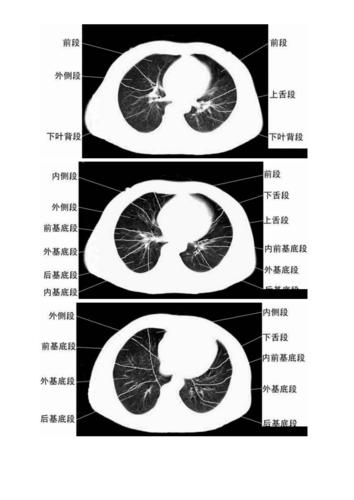

肺野如何划分

肺野如何划分,肺野的划分

肺野的划分

胸部ct肺段划分口诀doc

如何在ct上区分肺叶和肺段说课材料.ppt 17页

肺段的划分ppt

正常肺段的划分.doc

肺野的划分图

胸片肺野的划分

肺野分区

肺野分区图

肺段划分